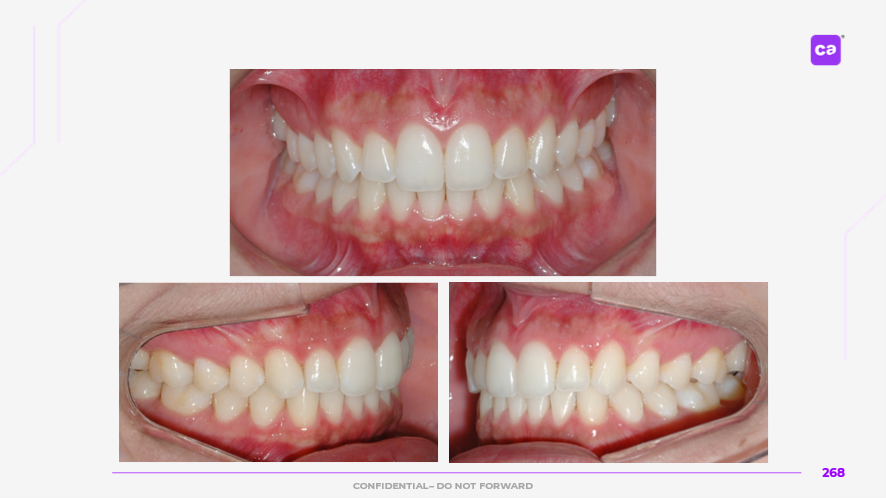

Figuras 3 – Fotos intraorais do caso clínico apresentadas em norma frontal e de perfil:

Na sequência apresentada, com os registros e comparação das fotos intraorais, observa-se a evolução do caso clínico desde a condição inicial até a finalização do tratamento com a conclusão do uso da série de alinhadores. Os resultados evidenciam a previsibilidade e acurácia do tratamento real em comparação às simulações e ao planejamento virtual inicial.

Observa-se a correção da sobremordida (mordida profunda), com avanço e torque vestibular dos incisivos superiores, juntamente com o nivelamento e alinhamento dentário das arcadas superior e inferior.

Além disso, nota-se o ajuste da linha média dentária superior, garantindo sua coincidência com a linha média inferior, bem como a otimização da curva e da estética do sorriso.